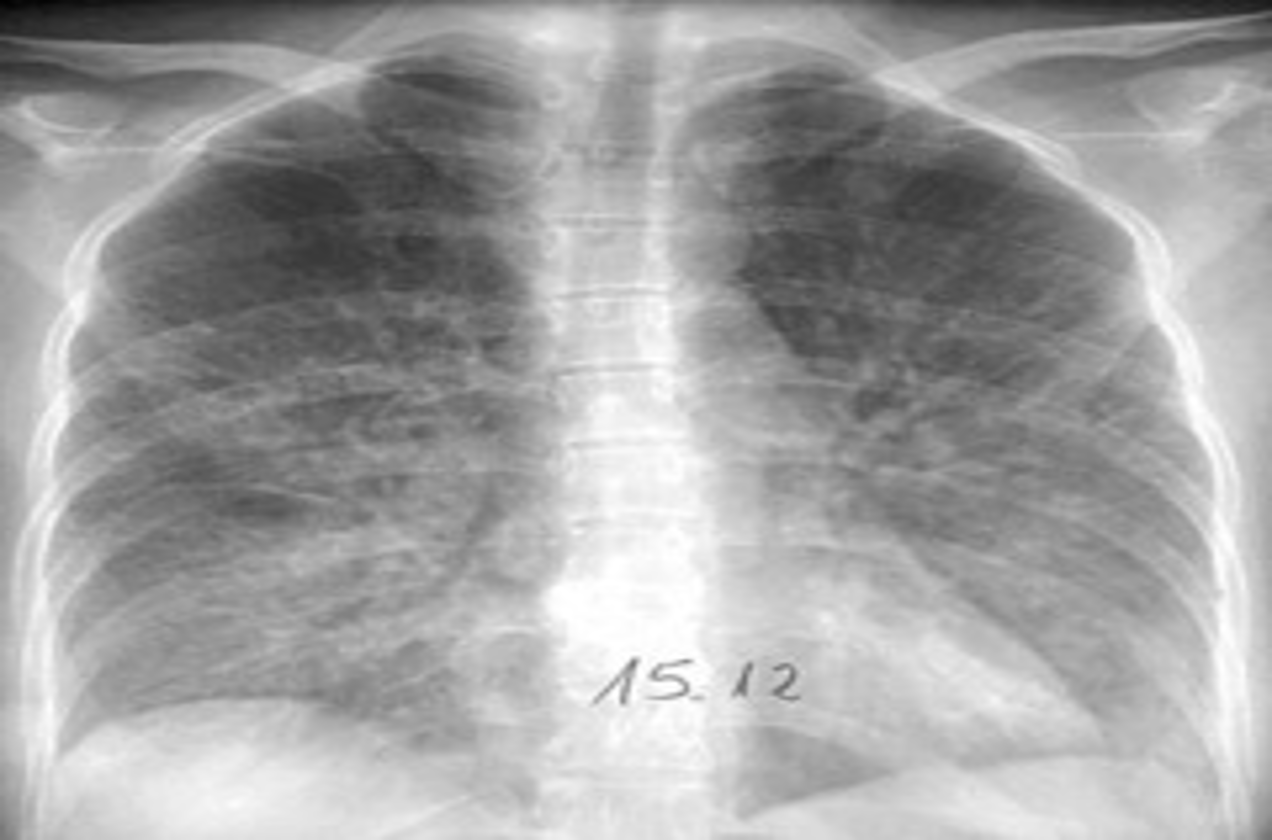

- Mycoplasma pneumonia: most commonly school age

- Patchy, segmental consolidation with hilar lymphadenopathy.

X-ray view of mycoplasma pneumonia